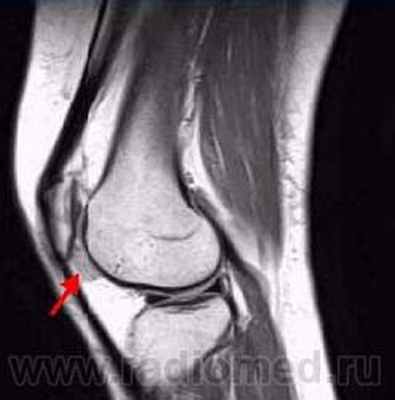

Пигментный виллёзонодулярный синовит - редкое заболевание с доброкачественным течением, характеризующееся пролиферативными изменениями синовиальной оболочки, отложением гемосидерина, образованием ворсинок, паннуса. Две разновидности: виллёзонодулярный бурсит и виллёзонодулярный тендосиновит. Частота - 2 на I 000 000. Преобладающий возраст • Виллёзонодулярный бурсит - 30-40 лет • Виллёзонодулярный тендосиновит -50-60 лет. Преобладающий пол - женский. Этиология. В 30% случаев развитию синовита предшествует травма сустава. Патоморфология. Пролиферация клеток синовиальных оболочек с образованием узлов, содержащих клеточный инфильтрат из фибробластов, лимфоцитов, макрофагов с жировыми включениями. Клиническая картина • Виллёзонодулярный бурсит -моноартрит. Чаще всего (80% случаев) поражается коленный сустав, реже - (с убывающей частотой) тазобедренный, голеностопный и плечевой суставы • Виллёзонодулярный тендосиновит - образование узелков в мышечных сухожилиях и связках сустава. Лабораторные исследования • Увеличение СОЭ • Синовиальная жидкость ксантохромная, с примесью крови • Биопсия синовиальной оболочки: узловая пролиферация, гемосидероз, инфильтрация мононуклеарными клетками. Рентгенологическое исследование • Остеопороз и наличие остеофитов нехарактерны • Артропневмография: множественные округлые дефекты наполнения синовиальной полости, обусловленные наличием узлов или гипертрофированных ворсинок синовиальной оболочки • МРТ - выявление гемосидерина и жировых включений. Артроскопия • Суставной хрящ приобретает коричневую окраску вследствие гемосидероза • Различной величины узлы коричневого цвета. Дифференциальный диагноз • Виллёзонодулярный бурсит • Липома - в аспиратах отсутствует ксантохромная жидкость • Остеоартроз - кисты возникают только на суставных поверхностях, подвергающихся нагрузке, тогда как при пигментном виллёзонодулярном синовите они образуются на всех суставных поверхностях. Остеофи-ты, напротив, более типичны для остеоартроза • Воспалительные арт-ропатии, дебютирующие моноартритом, - ревматоидный артрит, туберкулёзный артрит, анкилозирующий спондилоартрит и др. • Виллёзонодулярный тендосиновит - панглии (околосухожильные кисты): аспираты ганглиев содержат гелеподобную жидкость. Лечение хирургическое • Виллёзонодулярный бурсит • Тотальное иссечение синовиальной оболочки, вероятность рецидива заболевания составляет 25-40% • Лучевая терапия • Виллёзонодулярный тендосиновит - иссечение кист. Синоним. Синовит геморрагический МКБ. М12.2 Ворсинчато-узелковый (виллонодулярный) синовит (пигментный)

Результаты и их обсуждение артроскопии позволила дифференцировать характер поражения суставов у больных со сходной клинической картиной заболевания [9, 10], возможность изучить рельеф синовиальной оболочки на всем ее протяжении. В зависимости от давности синовита и особенностей его развития в данном суставе изменения синовиальной оболочки варьировали в очень широких пределах. Развитие воспалительного процесса в большинстве наблюдений сопровождалось ее утолщением, появлением гиперемии, пролиферации ворсин, образованием на ее поверхности фибриновых сгустков. Следует отметить, что одним из наиболее значимых параметров развития СХС может быть степень увеличения объема поражения синовиальной оболочки (СО), показателем который является выраженность ворсинчатой пролиферации [11]. Недостаточная эффективность внутрисуставных инъекций НПВП во многих случаях определялась относительной стойкостью к действию глюкокортикостероидов в результате значительного количества провоспалительных цитокинов в очаге воспаления [12]. В последующем нежная синовиальная оболочка трансформируется в довольно мощный тканевой массив (рис. 1).

Рис. 1. Выраженная ворсинчатая пролиферация, синовиальная оболочка превратилась в мощный тканевой массив. В суставе формируются пролиферативные изменения и сгустки фибрина. Произведено расширенная синовкапсулэктомия коленного сустава.

Рентген и Артроскопическая картина СХС коленного сустава, при урогенной этиологии (рис. 2-3).![]()

Рис. 5. А. Артроскопическая картина коленного сустава, при пигментно-ворсинчатом узелковом синовите (ПВУС). Б. После артротомии сустава.

В. Состояние хрящевого покрова. Хрящевой покров бедра и надколенника пропитан гемосидерином.